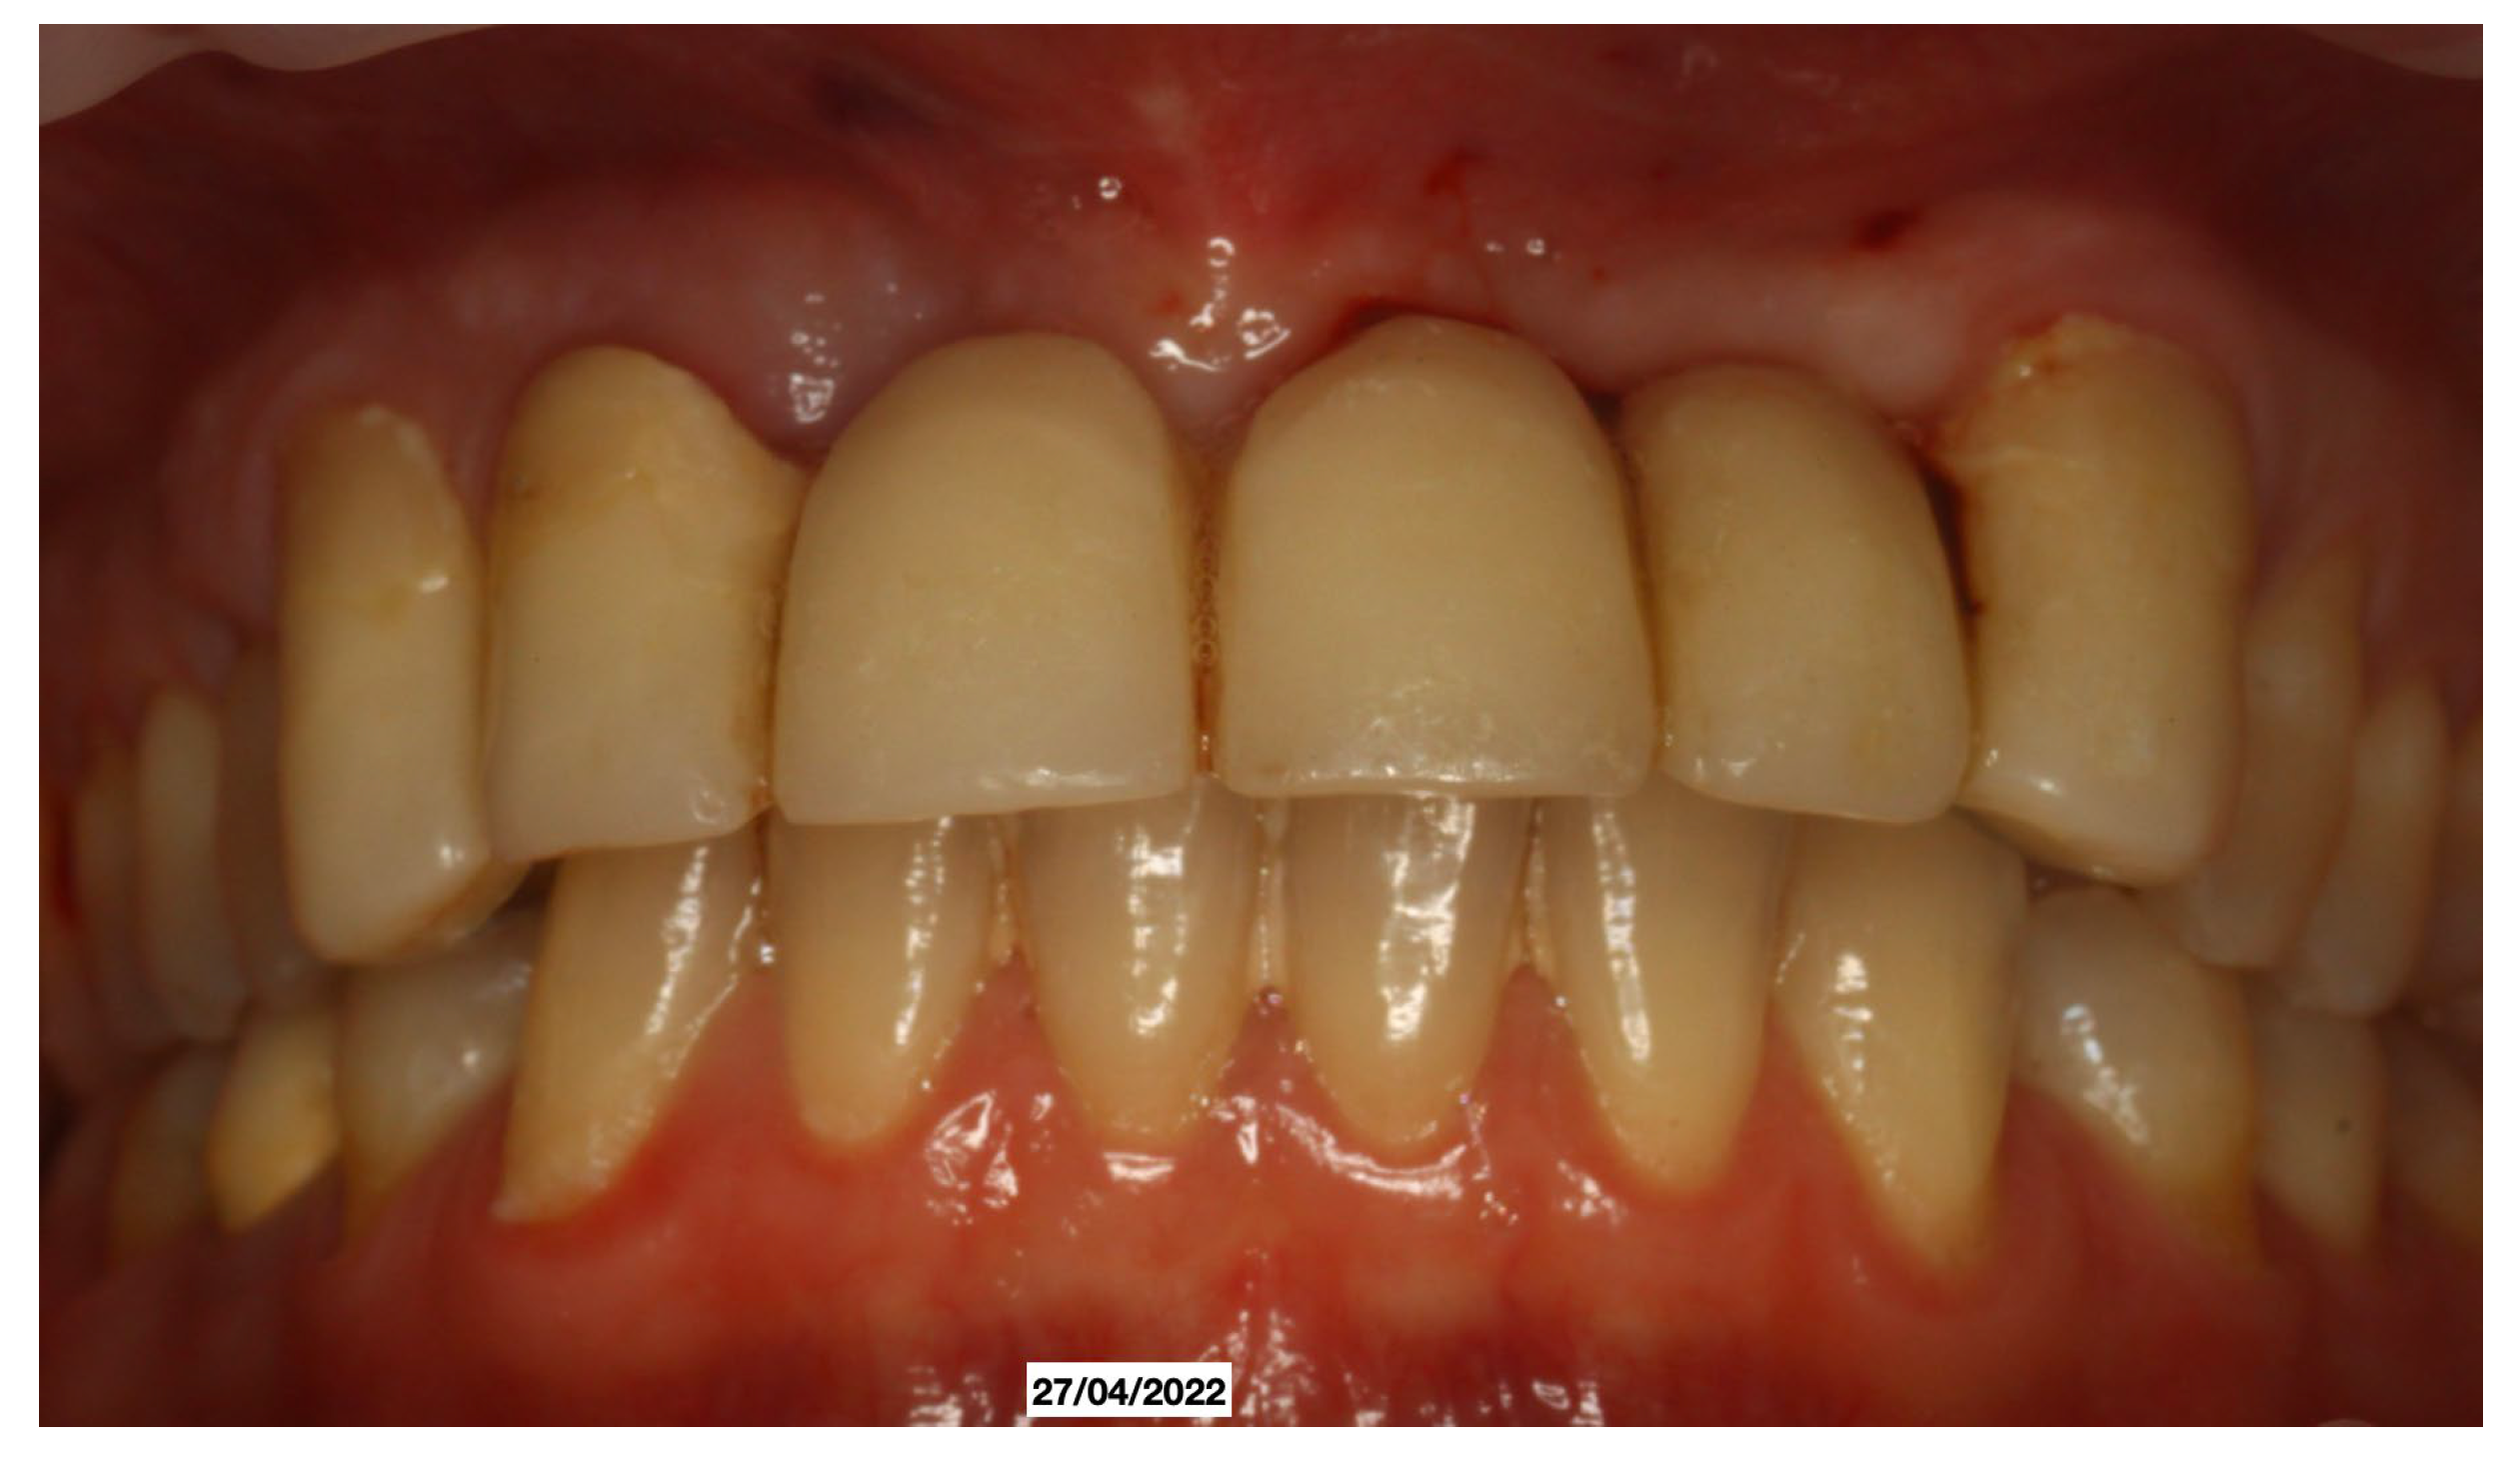

A 52-year-old patient, affected by non-Hodgkin lymphoma since March 2020 and treated with denosumab until June 2021, in clinical remission, presented in January 2022 for observation with multiple root resorptions, not of endodontic origin; it initially affected 22-21-11, but then, with rapid evolution, also affected 23-12-13-14-15-16-17-46-47, without referred pain. The resorption phenomena ended in September 2022. Since then, every radiographic check-up carried out to verify the progress of the regenerative bone surgeries has confirmed the arrest of the progression of the resorption phenomenon affecting the residual dental roots. In February 2022, as soon as responsibility for the patient’s care was assumed, in agreement with the oncology department of the hospital in Bergamo in which he was in care, given the severity of the lesions present (Figure 2), it was decided to extract the teeth (22-21-11), with a surgical toilet of the alveolus associated with decontamination with dye-free laser photodynamic therapy (February 2022).

Figure 2. Evolution of the external resorptions, with a rapid deterioration in only 2 weeks.